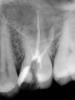

cleopa Опубликовано 2 ноября, 2013 Поделиться Опубликовано 2 ноября, 2013 уважаемые коллеги,нужен ваш совет. 26 зуб хронический пульпит. каналы очень узкие-в небный заходит только к-файл 10,в дистальный щечный - к-файл 06, в МВ1 никакой к-файл (ни 06,ни 08,ни 10) не заходит глубже,чем на 4 мм..устье МВ2 не нашла вообще. уже было 3 посещения, в результате которых обработала дистальный и небный каналы до 30.04 и 25.04 соответственно, (м-ту с 10 по 20 +профайлы 25.04 и 30.04) и запломбировала (АН+,гутта,лат.конденсация). МВ1 глубже,чем 4 мм пройти у меня не получается, пробовала в устье м-ту 10.04, 15.05, 20.06, а также пробовала пройти патфайлом 13.02, но глубже этих 4х мм они не идут (как я ни старалась, изменяла угол, изгибала инструменты, пробовала патфайлом вручную,все равно никакого результата). устье МВ2 так и не нашла, хотя уверена,что он там должен быть, придет пациент еще раз-опять буду искать.на RVG подозрительная анатомия медиального корня-мне кажется,что там 2 верхушки. снимки смогу прикрепить скорее всего не раньше вторника. поэтому у меня вопрос- что Вы делаете,когда инструменты "упираются как в стену" в корональной трети канала? Ссылка на комментарий

cleopa Опубликовано 6 ноября, 2013 Поделиться Опубликовано 6 ноября, 2013 (изменено) вот и снимки.пациент был еще раз,убирала навес медиально, искала-искала,но так МВ2 устье не нашла, МВ1 на той же стадии (4мм проходимости)..была там белая точка (на линии "соединения небного устья и устья МВ1),пыталась убрать ее уз насадкой-безрезультатно. п.с.без коффера-ждем инструменты.. Изменено 6 ноября, 2013 пользователем cleopa Ссылка на комментарий